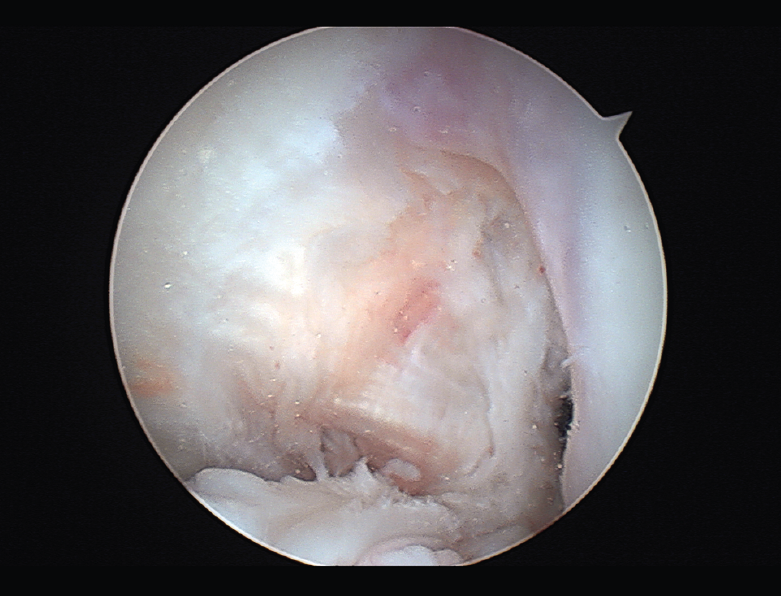

Un diagnóstico y una planificación correctos son fundamentales. En caso de rotura de plastia del LCA (Figura 3), se hace obligatoria, además de una detallada exploración, un correcto estudio radiológico completo que incluya radiología convencional y resonancia magnética (RM) –estudio de lesiones acompañantes o degeneración previa–. En ocasiones en donde la anamnesis/exploración lo justifique, pueden ser también necesarias telemetrías de extremidades inferiores, radiología forzadas (si existiera inestabilidad mediolateral) o tomografía axial computarizada (TAC) –valoración de la posición y la calidad de los túneles–.

Figura 3. Rotura de la plastia del ligamento cruzado anterior.